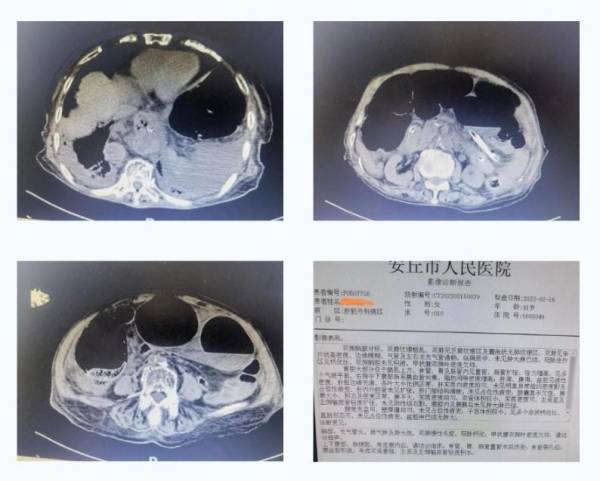

一般来说,患者术前要进行CT、磁共振等影像检查,医生通过阅片诊断确定病灶位置,为术前判断提供依据,确定相应手术方案。近日,安丘市人民医院肝胆外科病区救治了一位患有肠梗阻的9旬老人。影像科快速出具影像报告,外科主任通过影像诊断老人肠梗阻的原因是腹内疝(肠管扭转),并为老人实施了开腹探查手术方案。目前,老人已康复出院。

通常影像科的阅片工作量非常大,患者一次CT影像检查就要扫描几百幅甚至上千幅图像,医生需要对每幅图像进行阅片分析,每个细节都不能忽略,形成诊断报告,以便外科医生精准手术实施。